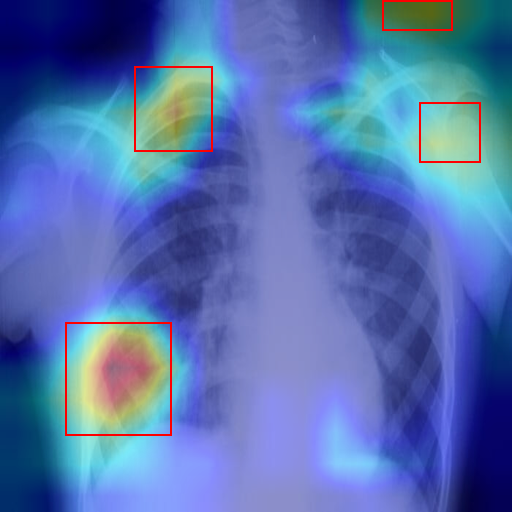

Thoracic X-Ray

Luna • Dog

2024-02-15

Atelectasis (86.2%) Completed